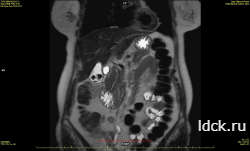

Результаты УЗИ. КТ не всегда достаточно информативны, в отличие от МРТ печени. Послойные срезы изображений органа дают врачу полное и четкое представление о процессах, протекающих в нем. Поэтому, хоть и цена МРТ печени выше распространенного УЗИ, томографическое исследование используется все чаще. На полученных снимкам видны: цирроз, опухоли, дистрофия, жировые перерождения, абсцессы, повреждения от травм и другие патологии.